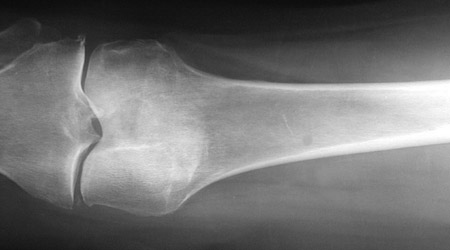

![]() | The rounded lucency seen here in the upper shaft of the femur is a plasmacytoma, a collection of plasma cells. In another case below, the lytic distal femoral lesion is more subtle. Since these patients had other lesions, this is not a solitary plasmacytoma, but multiple myeloma. His total serum immunoglobulin level was greatly increased, with an IgG "spike" seen on serum protein electrophoresis and bands of IgG and kappa on immunoelectrophoresis of serum. |